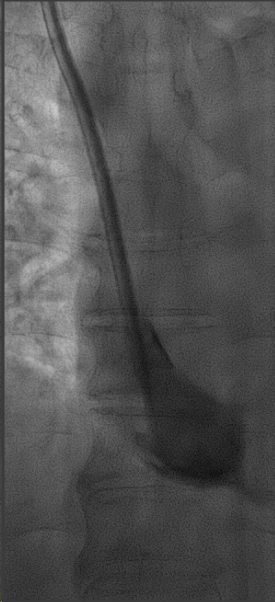

崔天蕾教授湍东运用经颈静脉肝内穿刺器械RUPS和房间隔穿刺针等多种手术器械,凭借精湛的技术和严谨的操作,克服了心脏搏动带来的干扰,成功在狭窄的穿刺区域中精确穿刺右心房,实现了上腔静脉闭塞处的导管再次植入。手术历时1小时10分钟,术后患者透析顺利,术后第三天出院。目前经过2个月的门诊随访,未见手术并发症及其他不适,该手术不仅为赵阿姨解决了透析通路的问题,也为血管通路的发展提供了新的思路和方法。

经右侧颈部再次植入透析导管后,造影显示导管末端在右心房